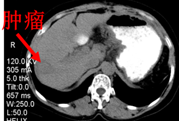

CT:符合肝硬化并脾大改变,肝右叶占位,胃底静脉及脾静脉曲张。

临床诊断:右肝占位性病变肝硬化、门静脉高压、脾大脾功能亢进食管胃底静脉曲张

术中穿刺病理提示:(肝右叶)肝细胞癌

消融后(术后1月)CT图像: